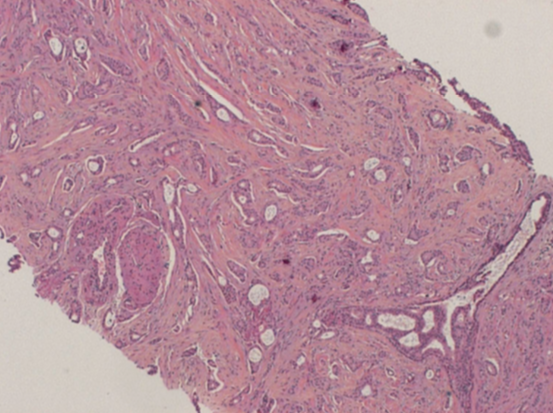

What type of breast cancer is shown?

Invasive ductal carcinoma